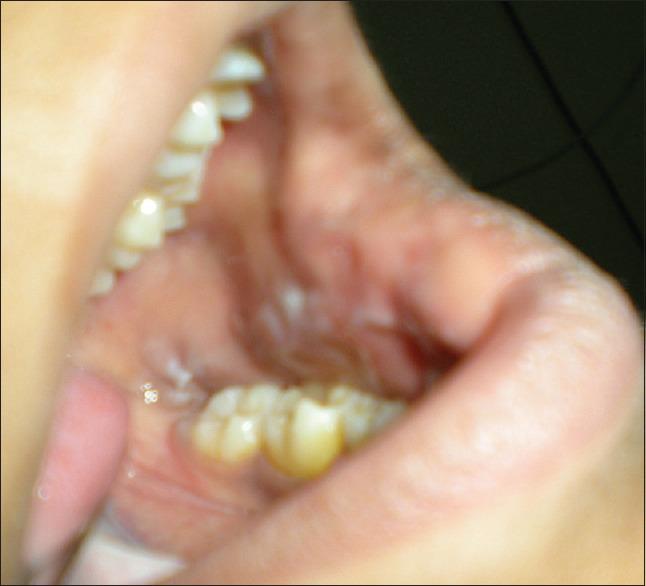

Buccal mucosal hypertrophy secondary to open bite.